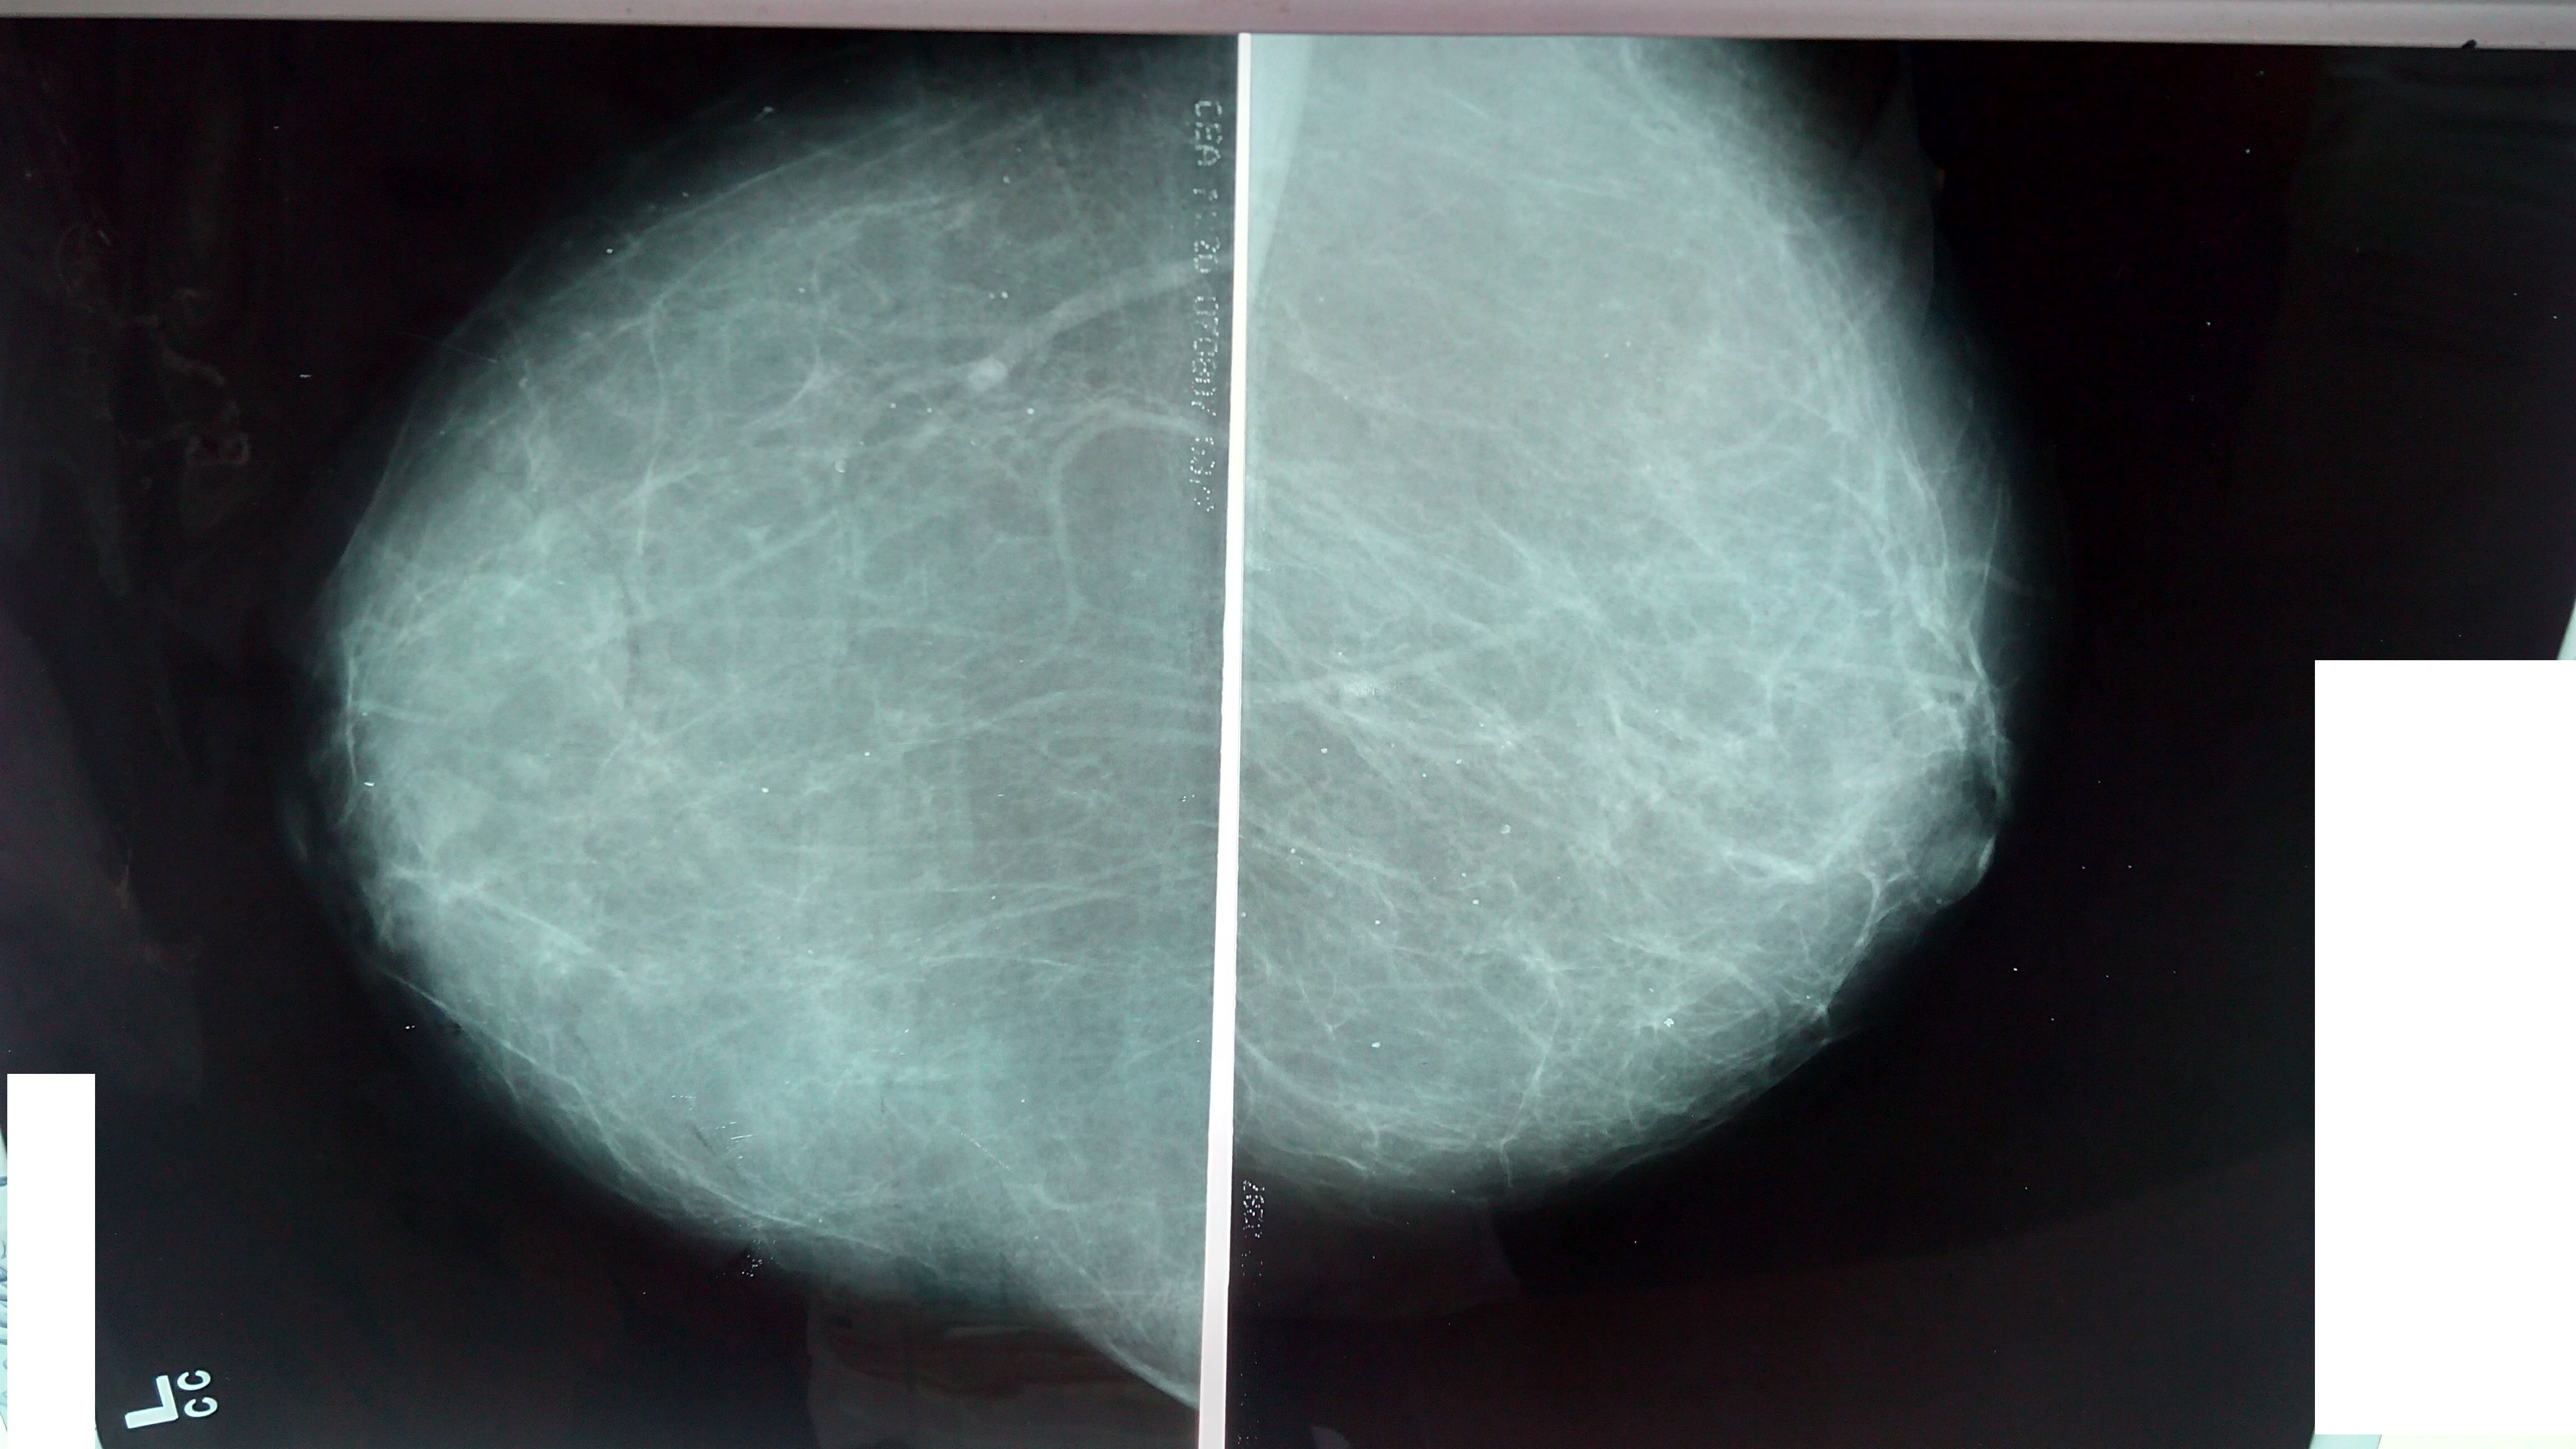

Фиброзно-кистозная мастопатия рентген молочных желез

Фиброзно кистозная мастопатия маммограмма